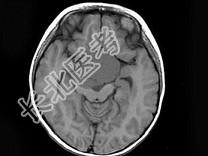

- 单项选择题女,51岁, 视力下降伴左侧面部麻木1个月,MRI检查如图所示, 应考虑为 ( )